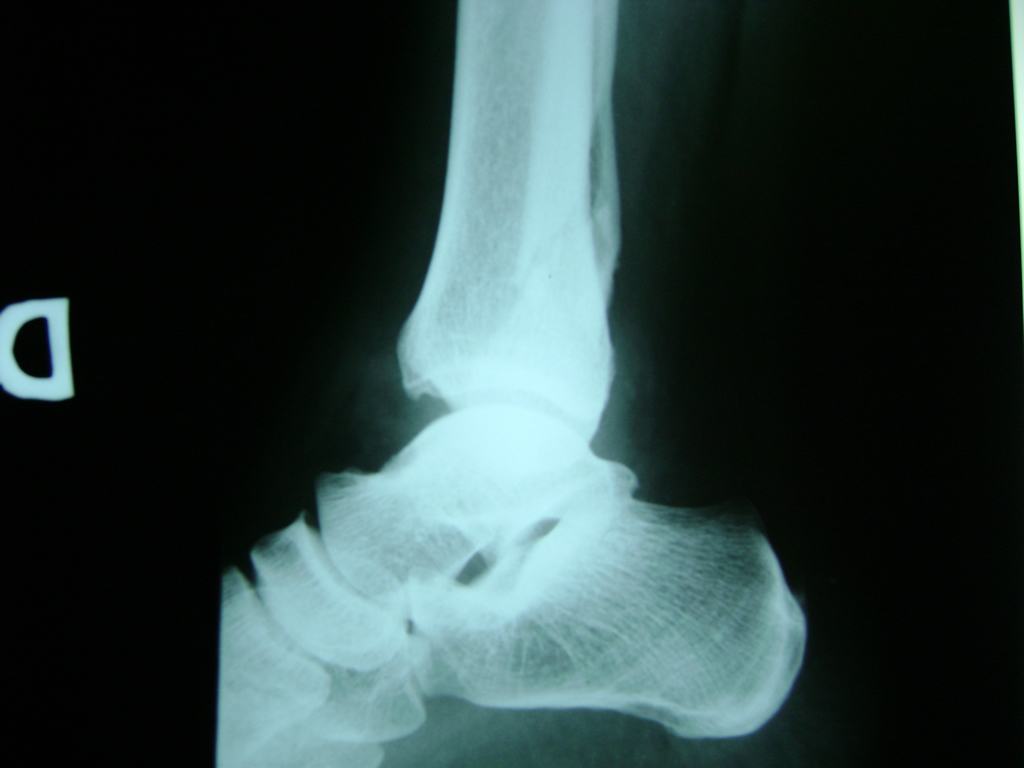

Una fractura de tobillo es la rotura de uno o más de los huesos del tobillo. Estas fracturas pueden ser:

Algunas fracturas de tobillo pueden requerir cirugía si:

Cuando se necesita cirugía, es probable que esta implique el uso de clavijas de metal, tornillos o placas para sostener los huesos en su lugar mientras la fractura se consolida. Los elementos de soporte pueden ser temporales o permanentes.